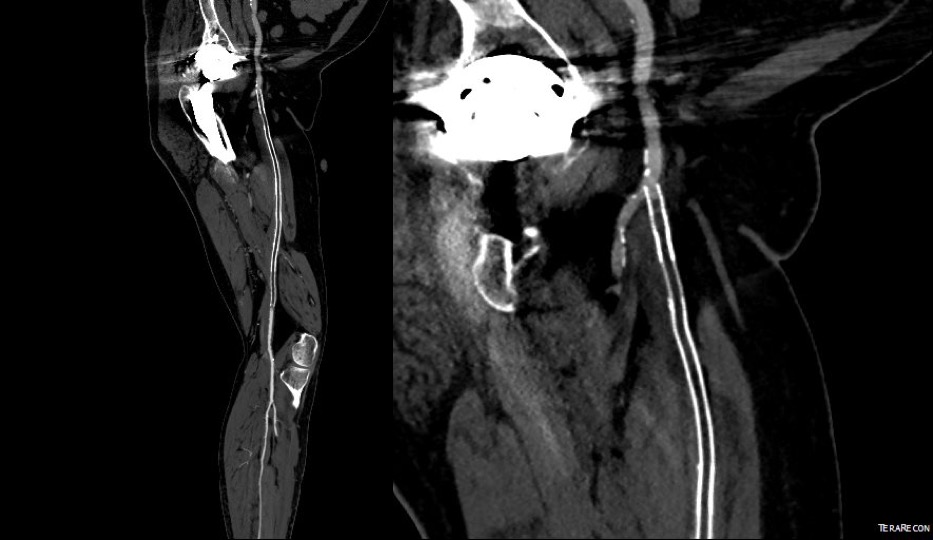

A postoperative CTA showed wide patency of the restored aorta and iliac arteries.

At followup several months after the procedure, the patient was walking well without claudicating and was ready to return to work. PVRs showed excellent flows down to the toes.